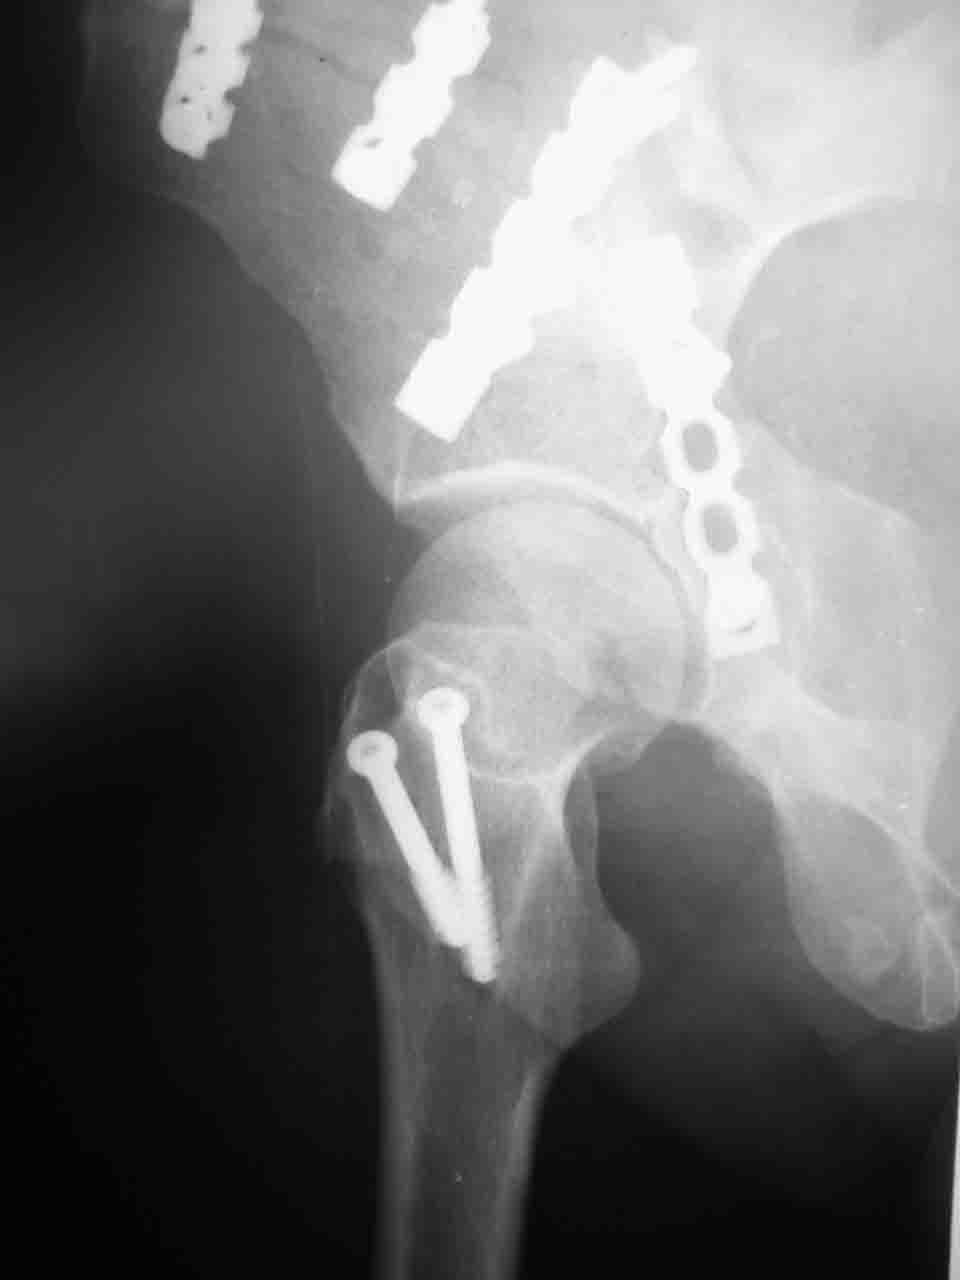

А какой отдел вертлужной впадины более важен передний или задний? Чем был обусловлен выбор доступа к суставу? Проще говоря, почему вы пошли передним доступом на двухколонный перелом? Мне понятны ваши сомнения, когда не удется сделать все что хотелось бы. В данном случае доступ должен быть чрезвертельным боковым (как и советовал Рунков) или двумя доступами.

Сложностью, ассоциативностью характера перелома, я бы с радостью воспользовался мининвазивной перкутанной фиксацией винтами, но боюсь, что результат был бы ещё хуже, техникой непрямой репозиции перелома не владею, поэтому пытаясь получить анатомичную впадину приходится широко открывать, по крайней мере пока, а дальше буду пытаться уменьшать пространство...

> передним доступом на двухколонный перелом?

Илеофеморальный доступ не совсем передний и сравнительно с илеоингвинальным, и Кохера-Лангенбека открывает весь наружный таз кроме самых передних отделов лонных костей, фиксацию которых я не ставил в задачу. Обширность диссекции, большая длительность операции и более высокий риск гетерооссификации - отрицательные моменты в обмен на возможность легче ориентироваться.

Комбинированные доступы - хорошая альтернатива, меньший процент осложнений, но я заметил , что без сбора *мозаики* безымянной кости сложно отрепонировать переднюю колонну, а с нерепонированной передней колонной невозможно анатомично собрать заднюю колонну и соотв. фрагменты стенки - так.что все равно открывать придется широко. Поэтому выбирая комбинированный

подход, передний доступ должен был бы быть продлен до задней трети крыла безымянной кости, а задний - практически до того же уровня, оставляя 6-7 см мостик. При этом вместо одного послеоп. рубца у больного остаются два сравнительно длинных.

Вопрос доступа к вертлужной впадине при остеосинтезе задача не простая. Конечно, у Летурнеля и Тайла всё давно описано, нам остается только брать на вооружение. Но сами понимаете, что не бывает двух одинаковых ситуаций, поэтому в каждом случае вопрос решается сугубо индивидуально. Наша главная цель - восстановить анатомию с нанесением минимальной дополнительной травмы тазобедреннному суставу, думаю с этим никто не поспорит. Расширенный илиофеморальный доступ уж слишком травматичен (как сказал один коллега "таз лежит отдельно, больной отдельно").Стоит ли делать из пациента анатомический препарат для того чтобы легче ориентироваться. Да и нужно ли собирать всю "мозаику"? Мы применяли при таких операциях своеобразную операционную хитрость - сначала устраняли грубое смещение крыла под гребнем с фиксацией так называемой "плавающей" пластиной (временно фиксированной на двух винтах)- доступ или продлевали боковой, или делали небольшой дополнительный разрез над гребнем. Это позволяло устранить грубое смещение и захождение отломков тела повздошной кости, что значительно облегчало репозицию и остеосинтез впадины над сводом. Основное внимание конечно же уделяли нагружаемому задне-верхнему отделу. Сообщите ваш адрес, пришлю схемы и рентгенограммы.